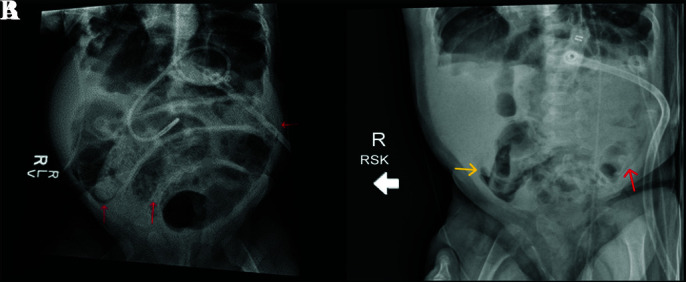

Pneumoperitoneum in infancy raises concern for visceral perforation and resultant urgent surgical exploration. However, benign pneumoperitoneum-defined as free intraperitoneal air without gastrointestinal perforation-can occur rarely, especially in infants with chronic ventilatory dependence. We present an unusual case of an 8-month-old infant with severe bronchopulmonary dysplasia (BPD), tracheostomy, and gastrostomy-tube dependence, with radiographic evidence of pneumatosis intestinalis and free intraperitoneal air. Diagnostic laparoscopy was performed which identified air within the mesentery of the small and large intestine, without evidence of true pneumatosis, perforation, inflammation, or ischemia. The patient recovered from their surgery uneventfully without any complications. This case highlights the importance of recognizing benign pneumoperitoneum, particularly in medically complex ventilator-dependent pediatric patients, and emphasizes the role of diagnostic laparoscopy as a valuable tool to confirm bowel integrity, preventing unnecessary laparotomy.